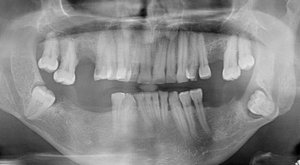

Восемь дней назад удалили нижнюю шестерку. Удаление было сложное, т.к. зуб был гнилой и ломался. Наложили шов и сказали, что его снимать не надо - "сам отпадет", и всё, что нужно делать - не мешать языком заживлению. Боль была сильная и отек не спадал, на пятый день пошла к другому врачу. Сказали, что внешне воспаления нет, а вскрывать жалко, прописали найз на три дня и ванночки настоя ромашки или хлоргексидина. Всё делаю, отек немного спал. Но соседняя пятерка всё еще болит и немного шатается, хотя недавно пломбу ставили, и всё хорошо было. Ещё какой-то неприятный привкус во рту стал, вроде кисловатый.